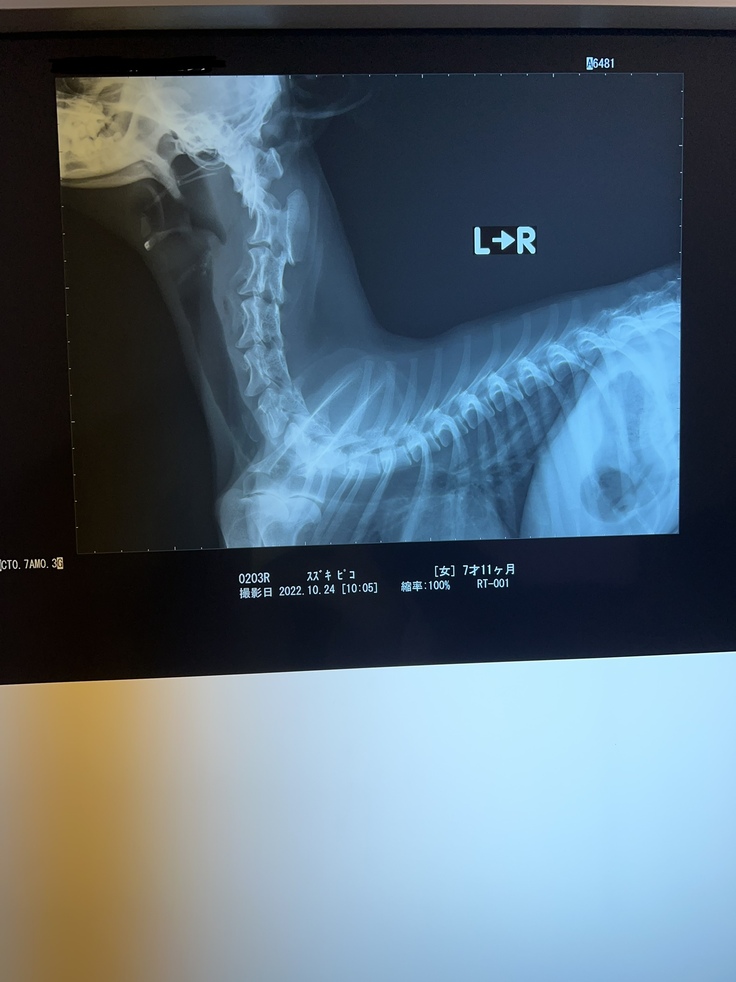

レントゲン、CT、MRIを撮ることに。

先天性の環軸亜脱臼である事が判明しました。

首の骨が脱臼しズレてしまい

脊髄を圧迫している状況

⬛︎レントゲン写真

骨が脱臼によりズレており脊髄を圧迫